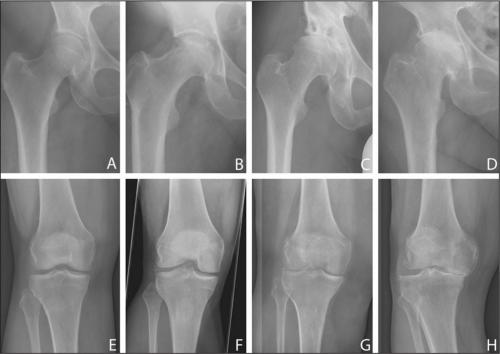

Стадии артроза коленного сустава. Обратите внимание на сужение суставной щели.

Все медикаментозные средства эффективны лишь—, но бессильныи IV. Если в патологию вовлечены не только суставы, но и кости, никакой препарат не поможет. В этом случае избавиться от хронических, трудностей при ходьбе, ограниченной подвижности суставов и других неприятных симптомов можно только с помощью операции.